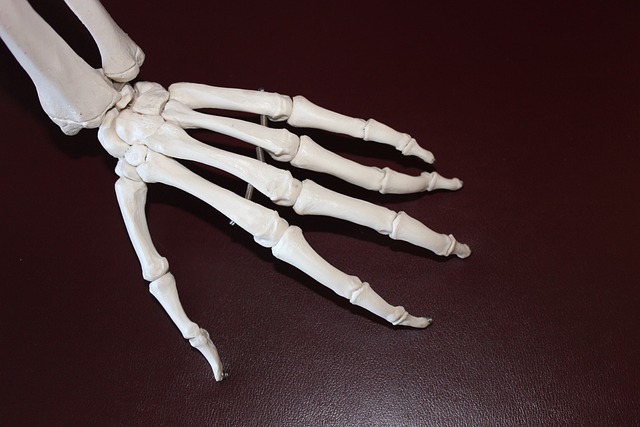

연골은 관절을 보호하는 부드러운 조직으로, 관절의 원활한 움직임을 돕고 충격을 흡수합니다. 연령 증가, 부상, 또는 특정 건강 상태로 인해 연골이 손상되거나 마모될 수 있으며, 콘드로이친은 이러한 연골의 손상을 늦추거나 관절 건강을 개선하는 데 도움을 줄 수 있습니다.

콘드로이친은 본질적으로 긴 사슬의 당류 분자인 글리코사미노글리칸의 일종입니다. 이 구조는 주로 연골 내에서 발견되며, 연골 세포 간의 공간을 채워주고 윤활 및 충격 흡수 기능을 제공합니다.

- 콘드로이친 황산염: 이 형태의 콘드로이친은 연골의 건강을 지원하는 데 사용되며, 황산 그룹이 붙은 긴 사슬 폴리사카라이드 구조를 가집니다. 황산 그룹은 콘드로이친이 수분을 끌어당기고 보유하는 데 도움을 주어, 연골의 탄력성과 충격 흡수 능력을 증진시킵니다.

- 수분 보유 증진: 콘드로이친은 연골 내 수분 보유 능력을 증가시켜 연골이 부드럽고 유연하게 유지되도록 돕습니다. 이는 관절의 움직임을 원활하게 하고 마모를 줄이는 데 중요합니다.

- 연골 보호: 콘드로이친은 연골 세포를 자극하여 핵심 연골 구성 요소인 콜라겐과 프로테오글리칸의 합성을 촉진합니다. 또한, 연골을 분해하는 효소의 활동을 억제하여 연골 손상을 늦출 수 있습니다.